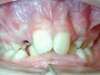

Fentes palatines bilatérales, cas traité au cabinet d'orthodontie du Dr Le petit à Bordeaux

Intra Orale Droite